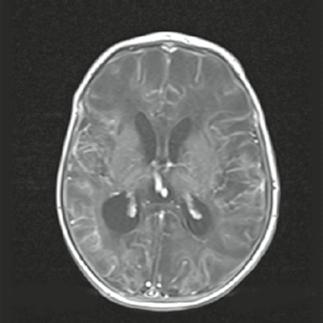

Muž, 61 let. Ischemie ve vertebrobazilárním povodí, dvakrát prodělal infarkt myokardu (IM), v anamnéze kardiomyopatie, hypertenze. Náhlá porucha vizu, nauzea, vomitus, hypakuze, vertigo, nemůže se sám postavit. Objektivní vyšetření: dezorientován, cerebelární syndrom vlevo, centrální vestibulární syndrom, levostranná hemiparéza.

Obr. A1.1–A1.4 Trombóza a. basilaris, akutní ischemické změny vertebrobazilárního povodí (pons, pedunculus cerebri medius dextra, parietookcipitální oblast).

Šipka v obrázku A1.2 – nezobrazilo se vertebrobazilární povodí